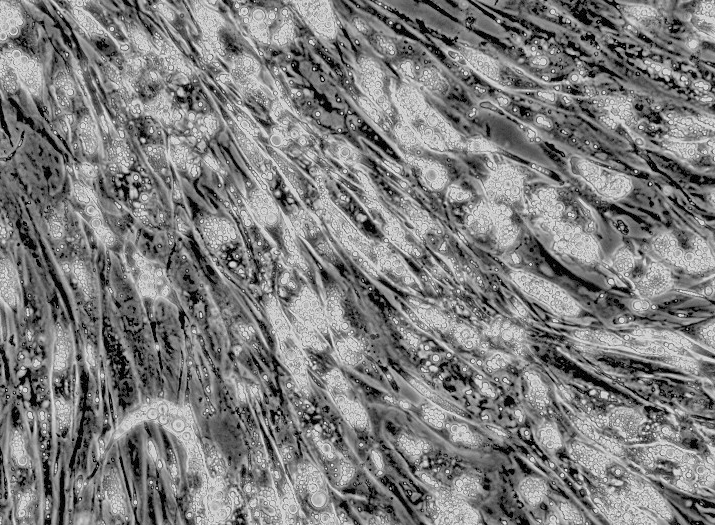

1.产品名称:Lovo人结肠癌细胞(通过STR鉴定)

2.组织来源:直结肠腺癌,转移位置:左锁骨上区

3.产品规格:1×10⁶cells/T25培养瓶